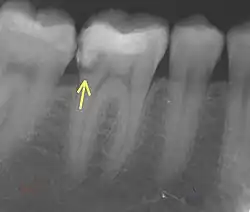

7. Radiographic examination

a. Periapical Radiographs

These provide detailed 2D images of the tooth and can detect fractures extending into dentin but may miss subtle enamel-only cracks due to their limited resolution.

b. CBCT

CBCT offers 3D imaging with high spatial accuracy, ideal for locating and assessing fractures extending into dentin or adjacent structures.